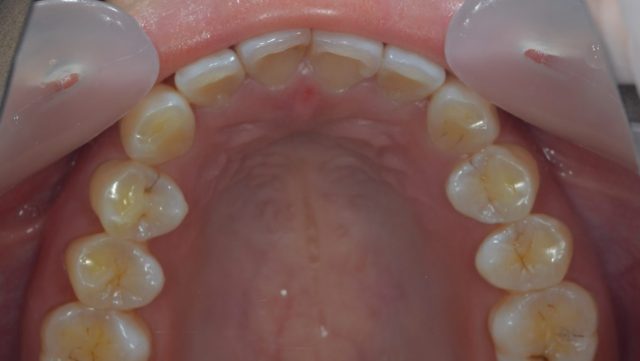

このボコボコしているのは骨隆起と言われ、歯にグーと力がかかったり

負担がかかっている人に見られることが多いようです!

通常はこのような形です。